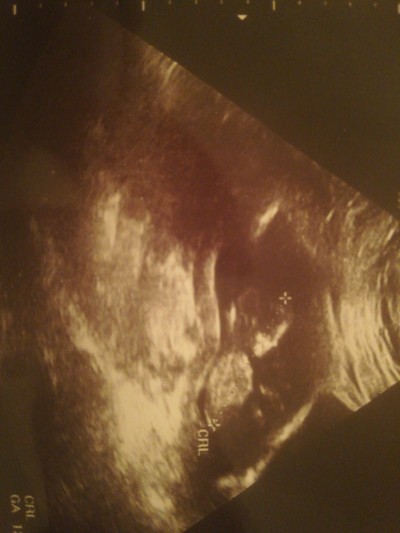

Arkadaşlar tahmin edebilen var mı acaba aranızda bir merak sardı beni

Gebelik haftası 14+5

Kıza benzettm cnm masallah

Ay erkek bu :)

Bugün öğrendim cinsiyeti tahmininiz doğru olmuş oğluşum oluyor :)